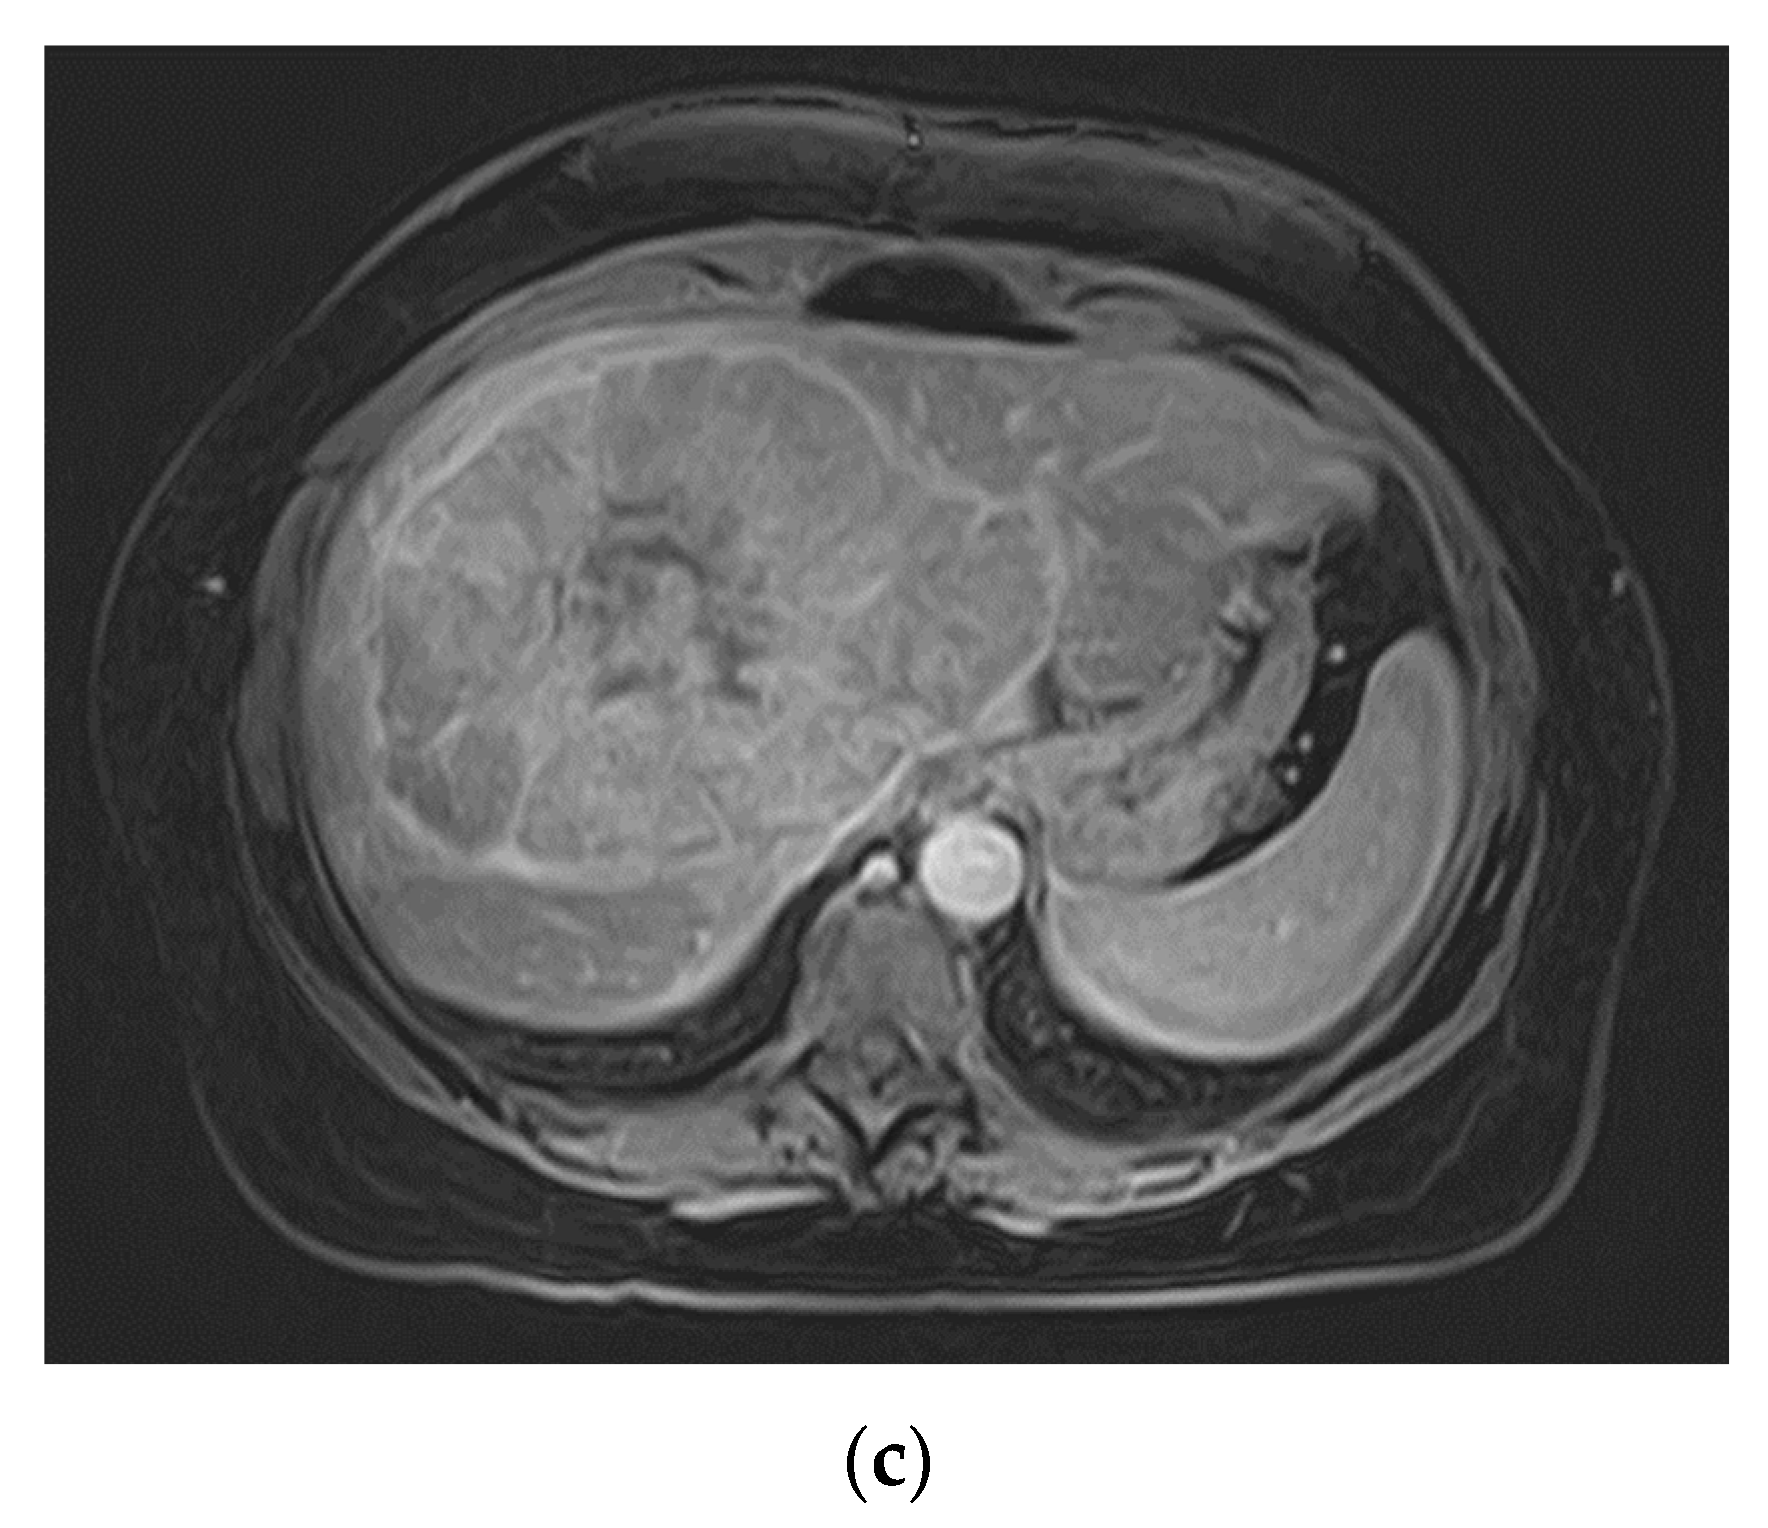

Figure 1. Pre-operative MR imaging Patient 1: (a) T2 TSE sequence depicting central scar; (b) T1 sequence with fat saturation in arterial phase depicting intense early arterial enhancement. (c/d) Slight signal drop in the tumor tissue (c) compared to healthy liver venous phase (d). No dedicated hepatobiliary imaging was performed.

The first patient was a 41-year-old female who was referred for a second opinion after receiving the diagnosis of a large FNH of the right liver lobe (Figure 1). AFP was within normal range. We indicated the explorative laparotomy due to a slight washout phenomenon in the venous phase which is not entirely typical for a FNH. Intraoperative frozen section showed a hepatocellular carcinoma and a bisegmental resection of the segments 5 and 6 (H56 according to the ‘New World’ terminology [6]) plus hilar lymphadenectomy was performed. Postoperative course was uneventful but early recurrence was diagnosed after four months and repeated resection was performed (H8′). A second recurrence led to a completion as formal right hemihepatectomy (H78) and subsequent treatment with Sorafenib. In the further course a local therapy with TACE was conducted after findings of a third recurrence. The patient passed away two years after the primary diagnosis of HCC.